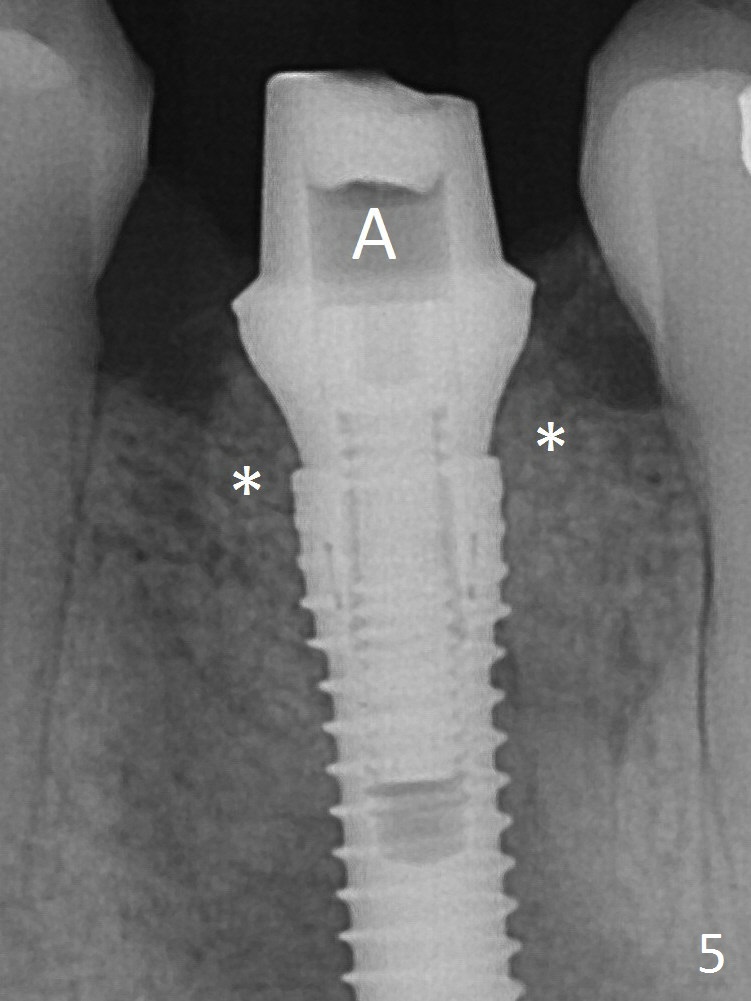

It appears that a 3.8x18 mm implant is not placed deep enough. Following 3-4 more turns of the implant and placement of a 5.5x4(3) mm abutment (Fig.5 A), allograft is placed (*).